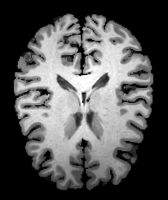

Results: All trained networks are evaluated using Dice overlap scores between predictions and the manual segmentations for the segmentation network, or between the warped moving segmentations and the target segmentations for the registration network. Tabs. 1 and 2 show results for the knee and brain MRI experiments respectively in Dice scores (%). Fig. 2 shows examples of knee MRI registrations and brain MRI segmentations.

Qualitative results: DA achieves more anatomically consistent registrations than the mono-networks on the knee (Fig. 2) and Brain MRI samples (see supplementary material).